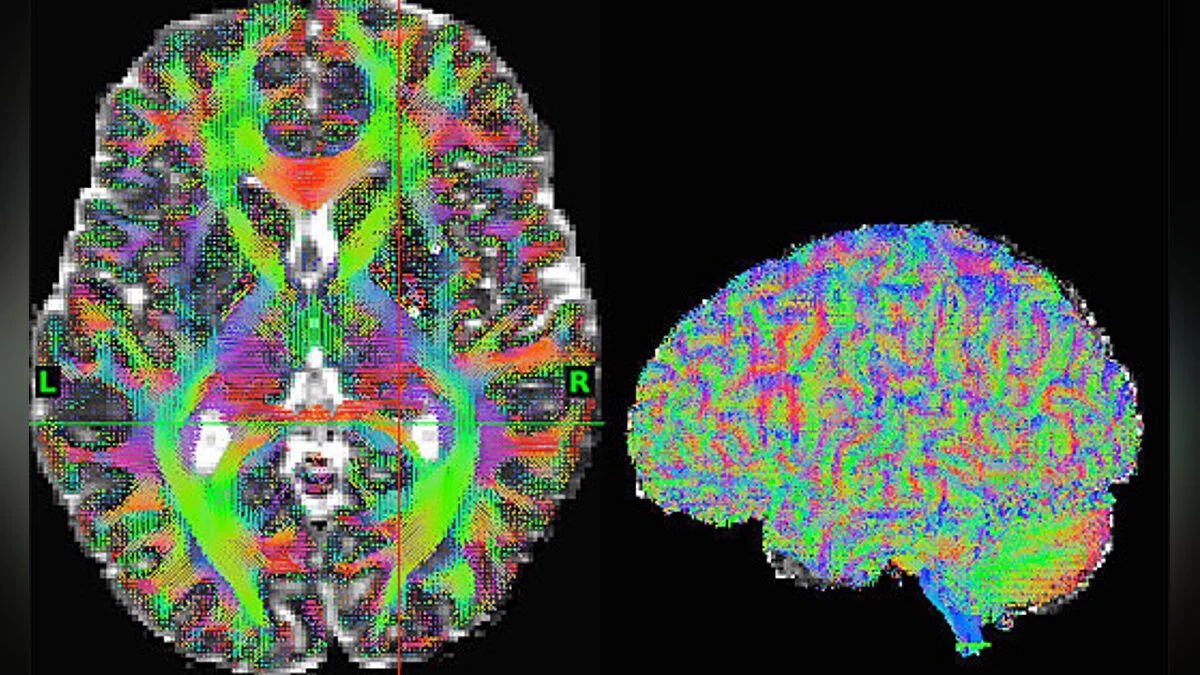

Недавно мы писали в новостях о том, что врачи провели первую в мире операцию на мозге с использованием ИИ. Благодаря технологии Human Connectome врачи отсканировали мозг пациента, проанализировали его и спланировали операцию так, чтобы выполнить хирургическое вмешательство через отверстие в черепе размером менее сантиметра. Ранее приходилось делать разрезы в 2,5-3 см.